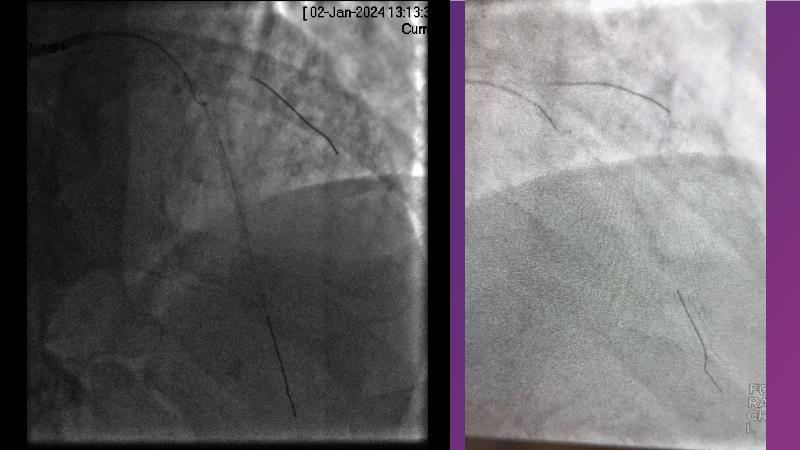

- To learn from the real world registries and complex cases to understand the practical implications and potential of the device in diverse patient population